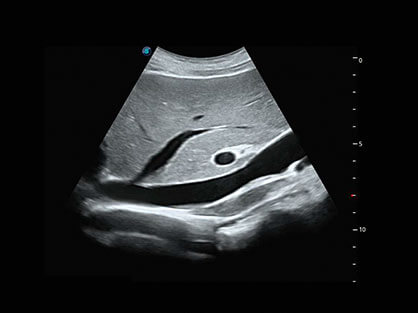

微米成像技术提升了对组织斑点噪声信号的抑制能力,并进一步强化边界信息,从而获得清晰图像。

通过对组织运动信息、血流信号及背景噪声进行准确智能的阈值判定,高效提取出微弱血流信号,获得高灵敏度和空间分辨率的血流图像,为临床提供更加真实和丰富的诊断信息。